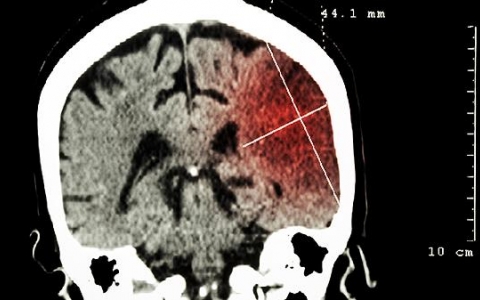

脑瘤的症状是什么

脑瘤患者会有头痛、呕吐、视觉障碍、精神症状、运动障碍等症状,需要及时治疗。1、头痛:大部分脑瘤患者会出现头痛症状,通常表现为慢性、持续性、加重的头痛。这种疼痛可

脑瘤吃什么中药可以控制

并不存在脑瘤吃什么中药可以控制的说法,因为目前临床上并没有治疗脑瘤的中药,患者出现脑瘤后可及时就医治疗。生长于颅内的肿瘤通称为脑瘤,包括由脑实质发生的原发性脑瘤